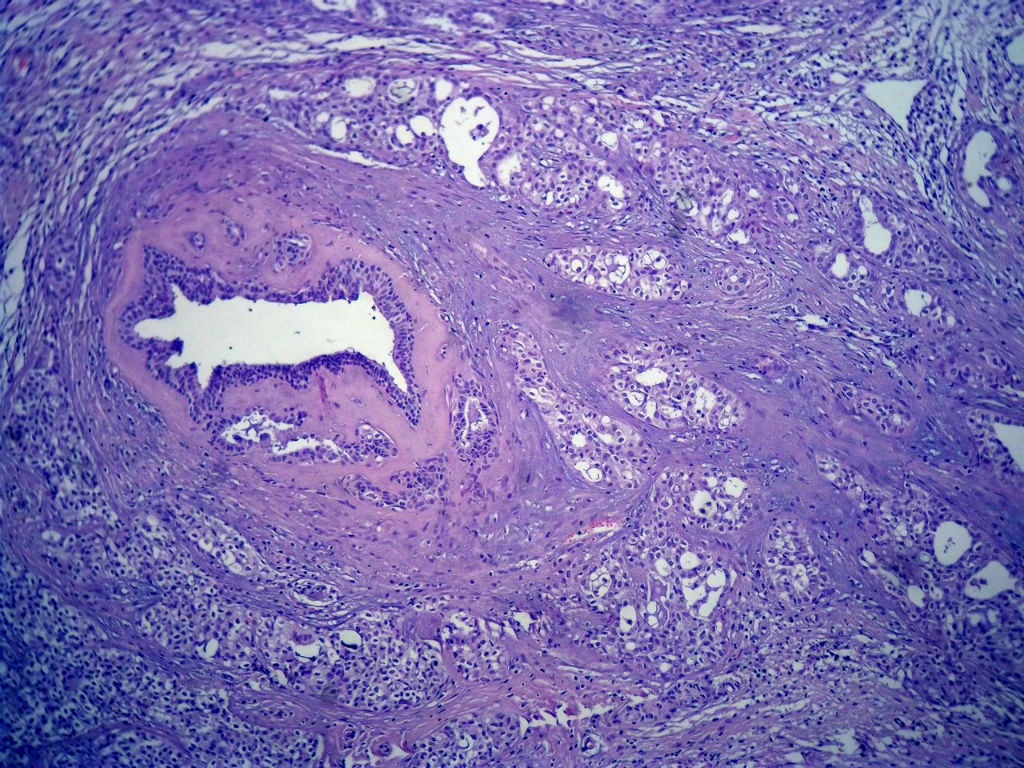

今天的一例术中冰冻。女,49岁,乳腺肿块。人气不旺,换个标题

腺病?癌?其他?(12楼常规,24楼免疫组化及会诊结果)图1

标签:浸润性导管癌 分泌癌 硬化性腺病

乳腺分泌型癌

1. Most likely no invasive cancer

2 Sclerosing adenosis

3 Ductal epithelial hyperplasia

4. Bundles d Smooth muscle?

导管是乎可见双层上皮,部分上皮增生并有一定异型,考虑硬化性腺病,待石蜡。

导管可见双层上皮,部分上皮增生并有一定异型,考虑硬化性腺病

腺体与腺体之间的对比差异太大,不放心,不除外是癌,如果是我的病例,再次取材冰冻

占楼传常规1-11为冰对。